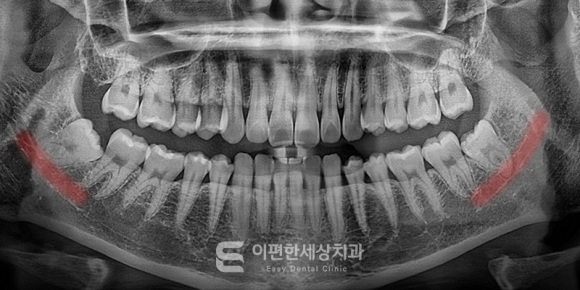

이해를 돕기 위한 참고사진입니다.

위 사진은 참고용으로 가져와봤는데요.

빨갛게 표시한 부분은 하치조신경으로,

사랑니의 치근이 신경과 밀접해 보이죠.

주로 환자분이 이런 상태일 때

사랑니 발치 경험이 적은 동네 치과나

고난도 케이스 발치에 자신이 없는 양촌향교치과라면

대학병원 내원을 권유할 수도 있습니다.